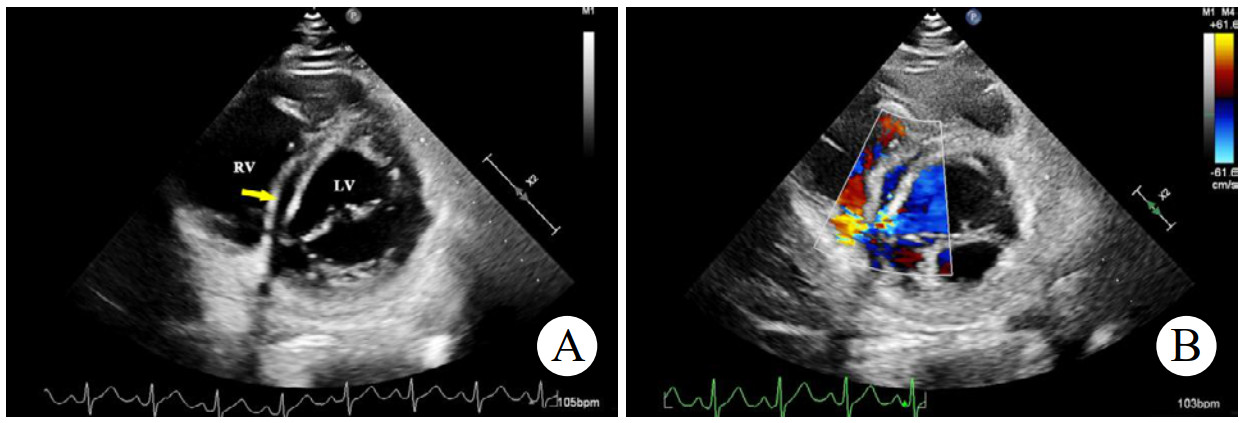

辅助检查如下。实验室检查:高敏C反应蛋白(hs-CRP)和红细胞沉降率(erythrocyte sedimentation rate, ESR)轻度升高。心电图:正常窦性心律,无ST段异常改变。胸部CT:双侧肺门中心对称分布的斑片状高密度影,部分实变,伴空气支气管征,病变边缘模糊。超声心动图:二维超声(2D)主动脉短轴切面显示右乏氏窦瘤破裂(ruptured of ASV, RASV),破入右心房形成“囊袋状”结构,长约1.7 cm,基底部破口内径约0.8 cm(图 1A)。彩色多普勒(color Doppler flow imaging, CDFI)显示全心动周期的左向右分流(图 1B)。连续多普勒(continuous doppler, CW)测得连续分流。室间隔内见4.0 cm×0.7 cm无回声区(图 2A),CDFI显示彩色血流信号随心动周期进出该无回声区(图 2B),考虑室间隔夹层瘤(dissecting aneurysm of the interventricular septum, DAIS)。实时双平面成像同步显示窦瘤破口与室间隔夹层相延续。应用Philips TrueVue三维(three-dimensional, 3D)超声心动图成像模式直观展示室间隔夹层瘤的立体结构(图 3)。

| 注:A为2D超声显示室间隔内无回声区(黄色箭头);B为CDFI显示彩色血流信号进出室间隔无回声区 图 2 2D及CDFI显示左室短轴二尖瓣水平切面室间隔夹层动脉瘤 |